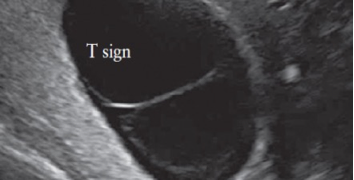

How To Do Settembre 2022: corretto settaggio del Doppler in ostetricia

Cari soci, questo mese un nuovo video "How to do", sul corretto settaggio del Doppler in Ostetricia. Grazie a Paola Quaresima! Il video è accessibile ai soli soci SIEOG attraverso...